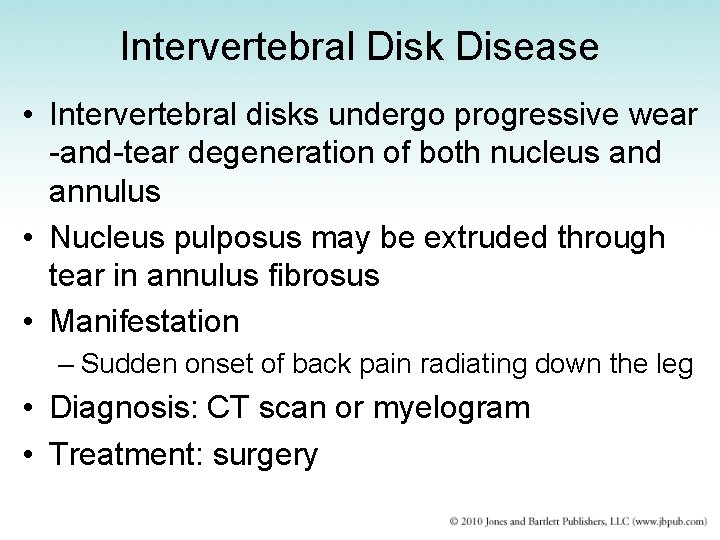

Intervertebral Disk Disease • Intervertebral disks undergo progressive wear -and-tear degeneration of both nucleus and annulus • Nucleus pulposus may be extruded through tear in annulus fibrosus • Manifestation – Sudden onset of back pain radiating down the leg • Diagnosis: CT scan or myelogram • Treatment: surgery